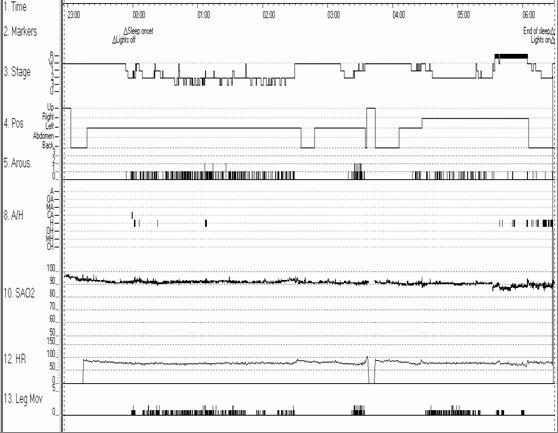

A 52-year old African American male with history of hypertension, Crohn’s disease, stroke, depression and multiple back surgeries presents for an assessment of sleep apnea to the sleep laboratory for an overnight sleep study. The hypnogram is shown below.

This hypnogram illustrates prolonged rapid eve movement (REM) latency of 341 minutes and decreased REM sleep (10%) with only one REM period before final awakening in the morning (red arrows). The sleep architecture also shows increased stage 2 sleep (64.2%) (green arrow). Although this patient was diagnosed with mild obstructive sleep apnea with an apnea-hypopnea index of 5 events/h, arousals (purple arrows) were predominantly non-respiratory related, and occurred secondary to the periodic limb movements (turquoise arrows) noted in the hypnogram.

Patients who are taking anti-depressants such as tricyclic antidepressants or selective serotonin reuptake inhibitors may have reduced REM sleep and a prolonged REM latency[1]. This patient was noted to have increased stage 2 sleep and decreased slow wave sleep which may be observed in the setting of benzodiazepine medication use [2,3]. This patient was also noted to have a significant number of arousals secondary to periodic limb movements which may be noted in patients with restless legs syndrome[4]. A potential secondary etiology of restless legs syndrome includes use of tricyclic antidepressants or selective serotonin reuptake inhibitors.